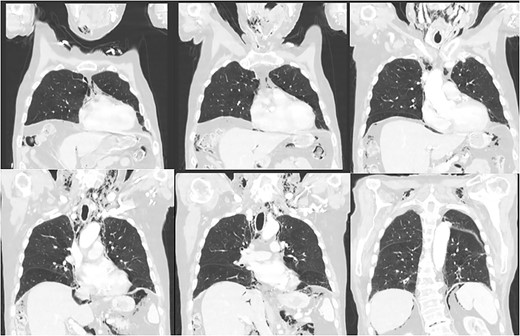

His vitals were stable on presentation. Physical exam was significant for weakness, tachypnea, and wheezing. He had no appreciable subcutaneous emphysema on clinical exam. Workup in the emergency department was remarkable for increased white blood cell count (17.0 K/uL). EKG showed no acute changes and cardiac enzymes were within normal limits. Computed tomography (CT) of the chest, abdomen, and pelvis with contrast was obtained, demonstrating acute sigmoid diverticulitis with extensive retroperitoneal air originating next to the sigmoid colon and multiple small collections of fluid. The pneumoretroperitoneum was continuous with pneumomediastinum and cervical emphysema (Figs 1 and 2). He was diagnosed with perforated diverticulitis and operative intervention was recommended.

CT scan of the chest demonstrating subcutaneous emphysema and extensive free gas in the mediastinum and retroperitoneum.